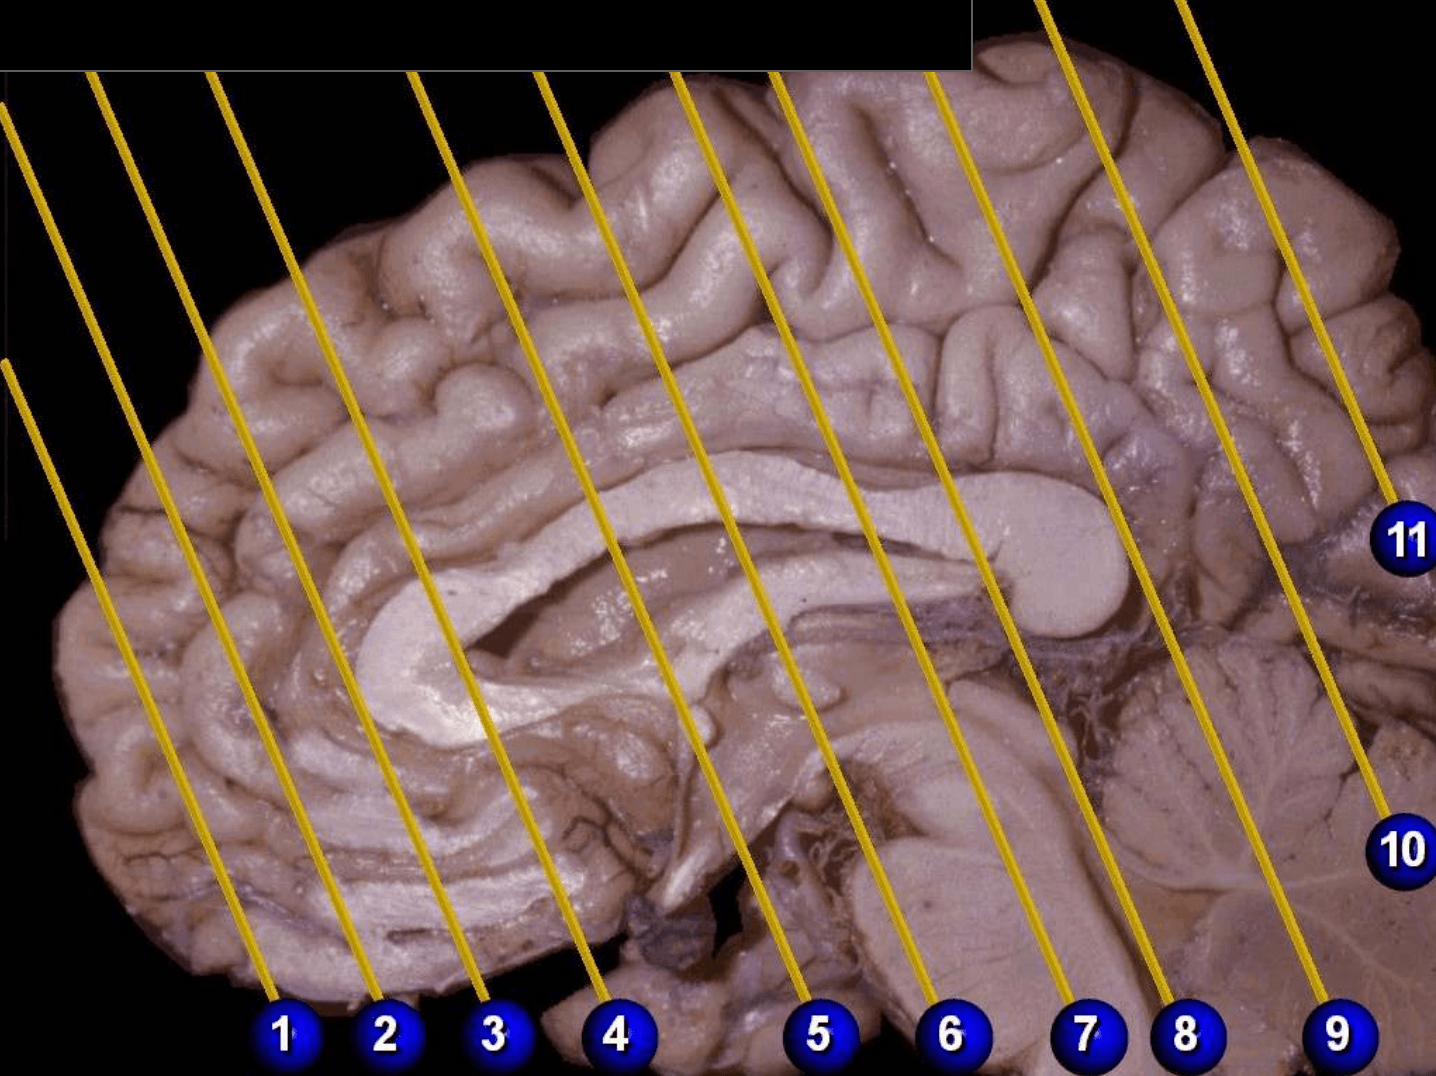

Tronco del cuerpo calloso

Rodilla del cuerpo calloso

Columna del fórnix

Comisura anterior

Foramen interventricular

Infundíbulo

Habénula

Pico del cuerpo calloso

Acueducto del mesencéfalo

Estría medular del tálamo

Adhesión intertalámica

Lámina terminal

Quiasma óptico

Tubérculo mamilar

Comisura posterior

Glándula pineal

Rodete del cuerpo calloso

Calota mesencefálica

Túber cinereum